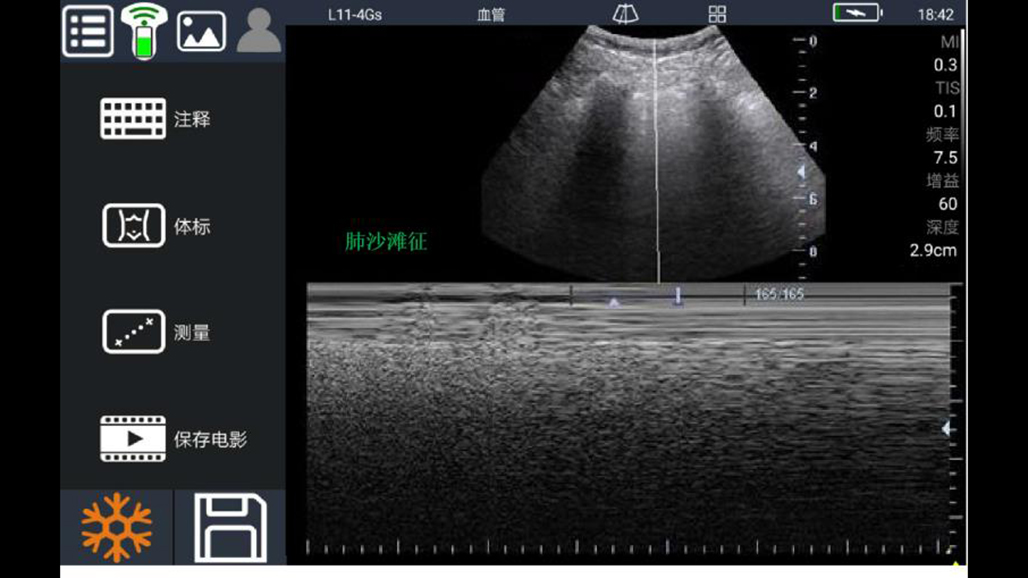

• 大凸

心脏

肺等